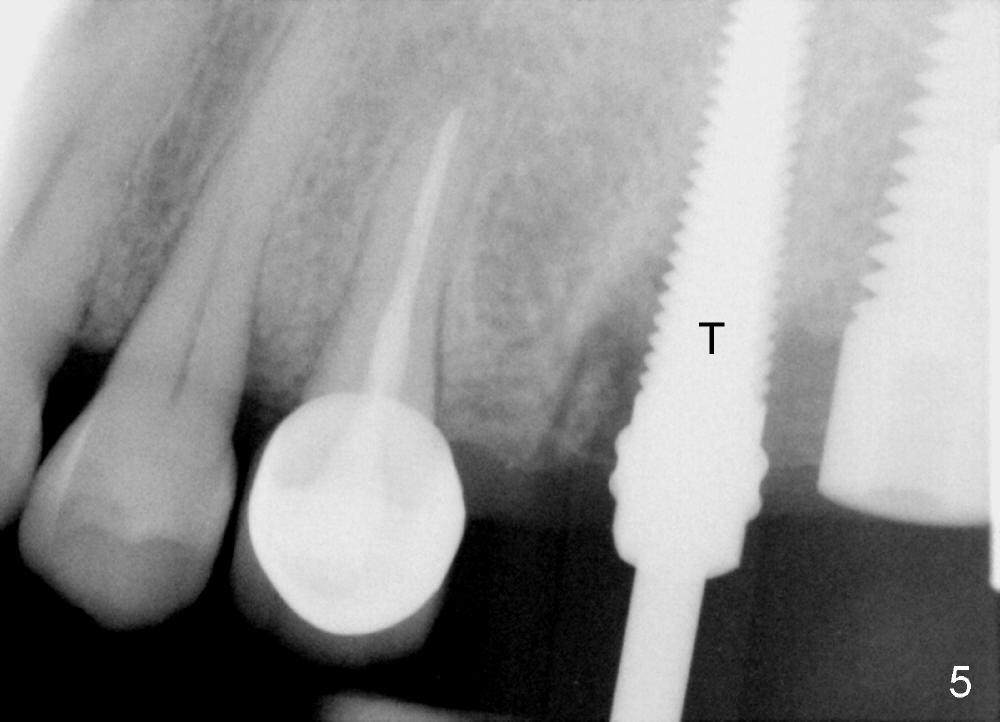

Fig.4 shows the septum between 3 roots (P: palatal, MB: mesiobuccal, DB: distobuccal) after extraction. Osteotomy is formed in the septum mainly by using osteotomes, followed by tap drill (Fig.5: 4.5x20 mm). When a 5x20 mm tap is removed, the osteotomy deviates buccally (Fig.6 arrowhead and MB). Finally a 5x20 mm implant is placed at the site of #14 (Fig.7).